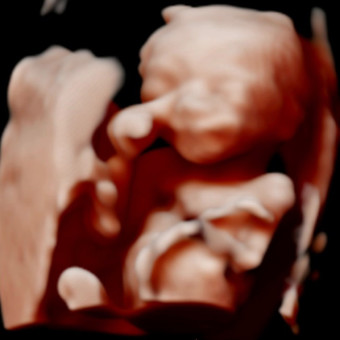

Baby Delgado Registry

Alex Rodrigues & Delgado Delgado

June 21, 2026